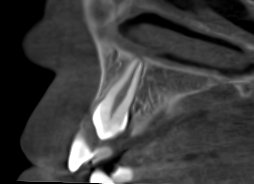

Los dientes incluidos, como caninos o muelas del juicio, son una situación frecuente en odontología. Aunque la ortopantomografía suele ser la primera prueba diagnóstica, en muchos casos no ofrece información suficiente para planificar el tratamiento con seguridad, especialmente cuando existen dudas sobre la posición real del diente o su relación con estructuras cercanas.

Al tratarse de una imagen bidimensional, la panorámica puede presentar superposiciones y distorsiones que dificultan la interpretación. En estos casos, el CBCT (Tomografía de Haz Cónico) permite un estudio tridimensional preciso, aportando la información necesaria para una correcta toma de decisiones clínicas.

El CBCT proporciona una visión 3D completa que permite:

- Localizar el diente incluido con precisión.

- Evaluar su angulación y cercanía a otras piezas dentarias.

- Detectar posibles reabsorciones radiculares.

- Planificar extracciones o tracciones ortodóncicas con mayor seguridad.

Esta información es especialmente relevante en caninos incluidos, donde una planificación adecuada reduce riesgos y mejora el pronóstico del tratamiento.